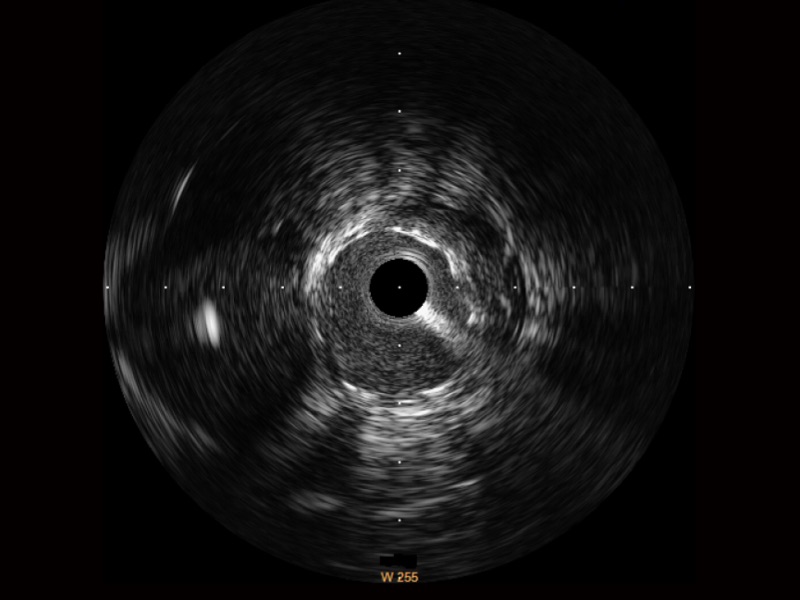

1xBET宽频IVUS图像

传统IVUS图像

对比传统IVUS导管成像,1xBET宽频IVUS图像的近场支架梁显影更细腻,远场中膜外血管仍清晰可辨,兼顾远中近,兼顾分辨力与穿透深度